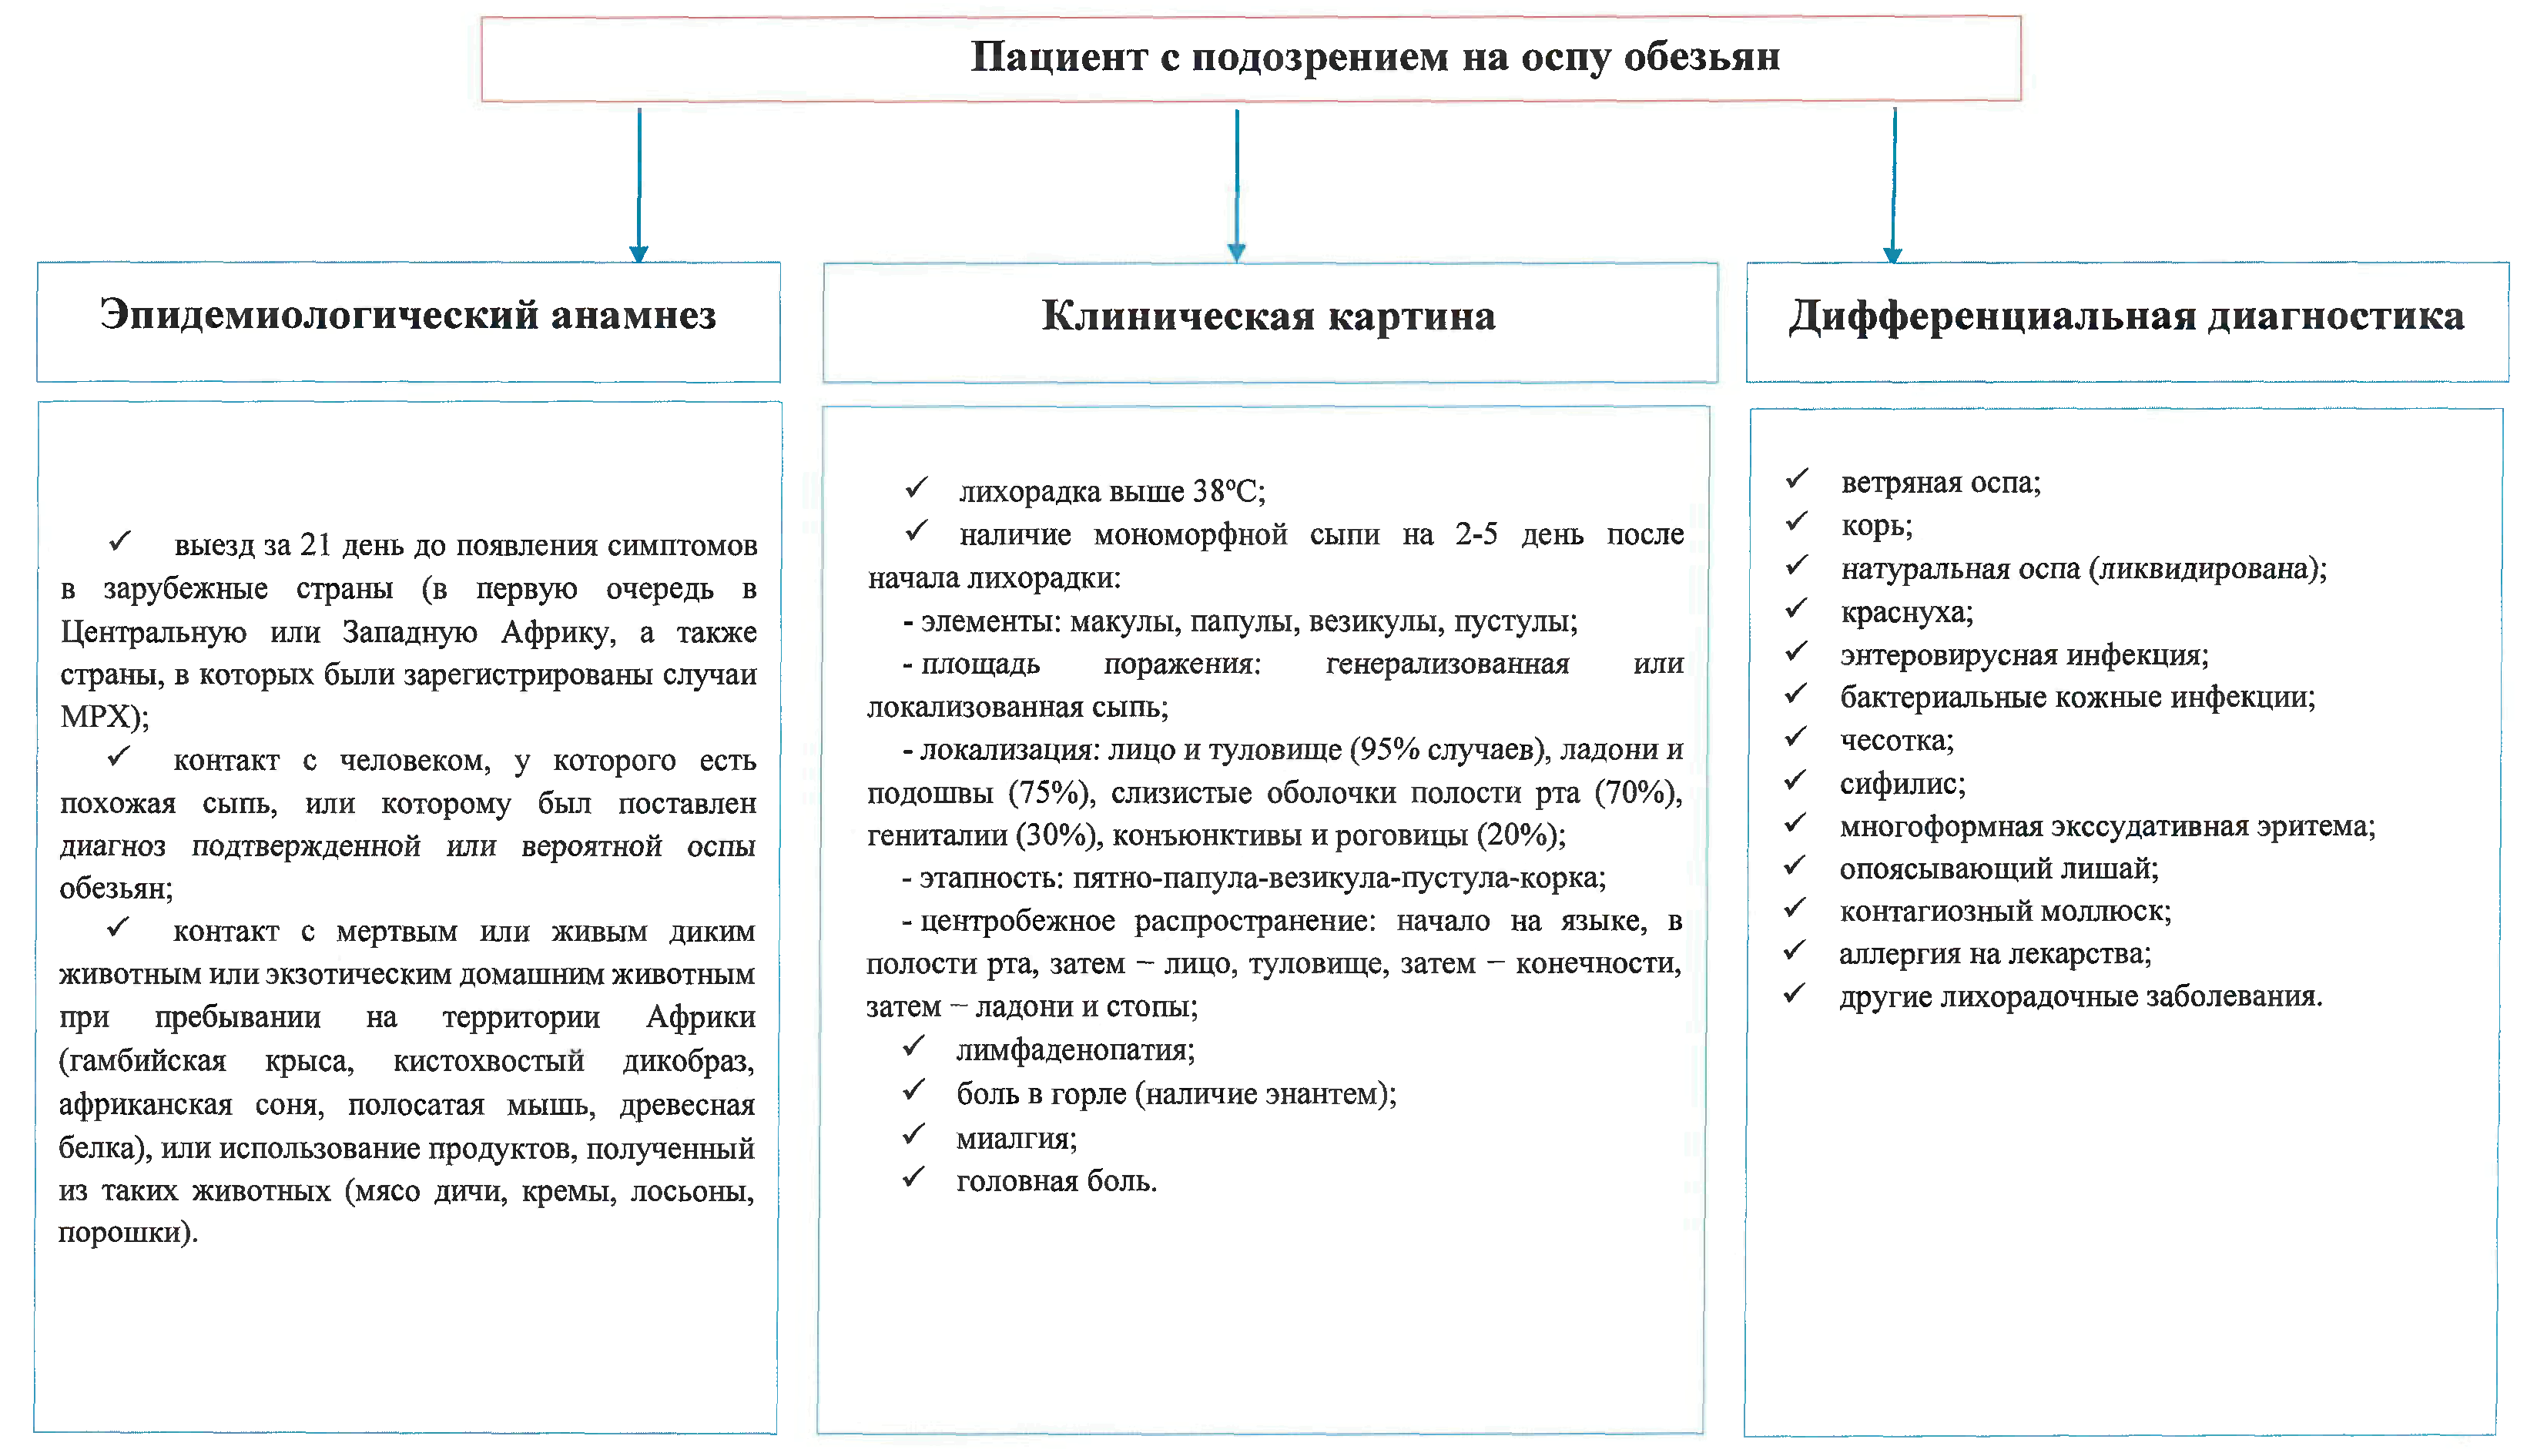

Алгоритм клинической диагностики оспы обезьян

Приложение 2.1